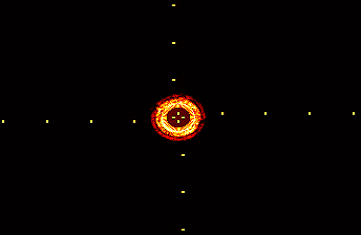

To use EREL, we need to set several initialization parameters, namely , , , . These parameters define the functionality of the detector and can be tuned based on the application [16, 15]. In particular, we use , to set the minimum and maximum area of the extracted regions. To better separate small regions from bigger ones, we choose a value for that correlates with image dimensions. Specifically, we set and where and represent the number of rows and columns of the IVUS image, respectively. The parameter is usually in and represents the strength of the resulting interest points [16]. In this study we set . Finally, denotes the width of the moving window over the global criterion vector [16]. The extracted EREL regions using the above-mentioned values are illustrated in Figure 2.

However, not all four types of the regions depicted in Figure 2 encompass lumen and media regions. In fact, we only need to extract large area regions as illustrated in Figure 2(d). Since large area regions contain the actual lumen and media segments, detectors need not track regions and, therefore, omit unnecessary computations which eventually helps to have a faster detector.

2.5 EREL Selection

The goal of this section is to address the problem of finding the most appropriate ERELs to be designated as lumen and media. By the most appropriate we mean the closest regions to the gold standard. As can be seen in Figure 2(d), although ERELs are nested regions, it is clear that there is at least one EREL that is very close to the true lumen and similarly there is at least one EREL that corresponds to the true media. Therefore, we can relax the problem of lumen and media segmentation to only a selection procedure, i.e., assigning two nested ERELs to lumen and media.